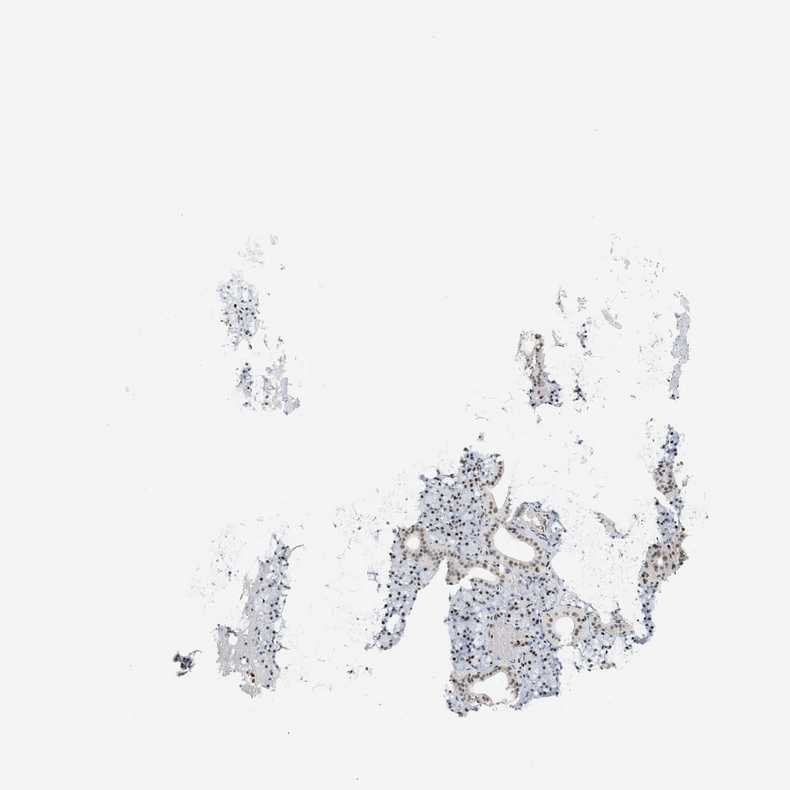

SALIVARY GLAND - Antibody stainingi

Antibody staining in the annotated cell types in the current human tissue is reported as not detected, low, medium, or high, based on conventional immunohistochemistry profiling in selected tissues. This score is based on the combination of the staining intensity and fraction of stained cells.

Each image is clickable and will lead to virtual microscopy that enables deeper exploration of all samples and also displays staining intensity scores, fraction scores and subcellular localization as well as patient and tissue information for each sample.

Antibody HPA022961Antibody HPA024457

Glandular cells HighHigh